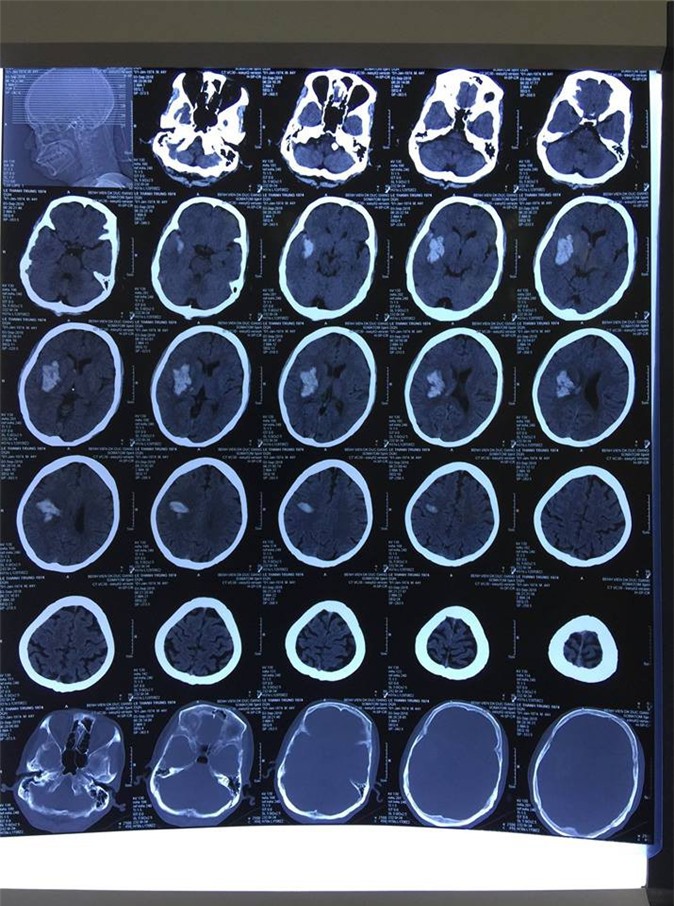

(DNVN) - Ngày 3/10, Bệnh viện đa khoa Đức Giang ( Hà Nội) thông tin: Đã thực hiện ca cấp cứu kịch tính, với 3 giờ đồng hồ phẫu thuật căng thẳng, kịp thời cứu sống bệnh nhân nam Lê T.T nguy kịch do xuất huyết não.